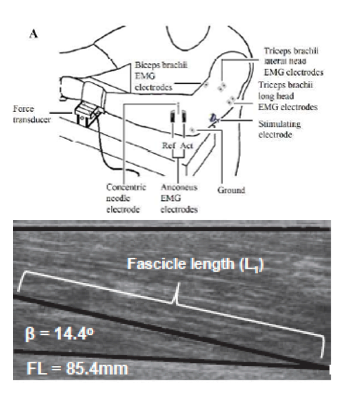

Research studies in my lab are directed at describing and understanding muscle contractile output (force or torque) in relation to neural activation and motor control of the muscle. We study these aspects in humans at a systems level with an integrated approach using minimally invasive techniques.